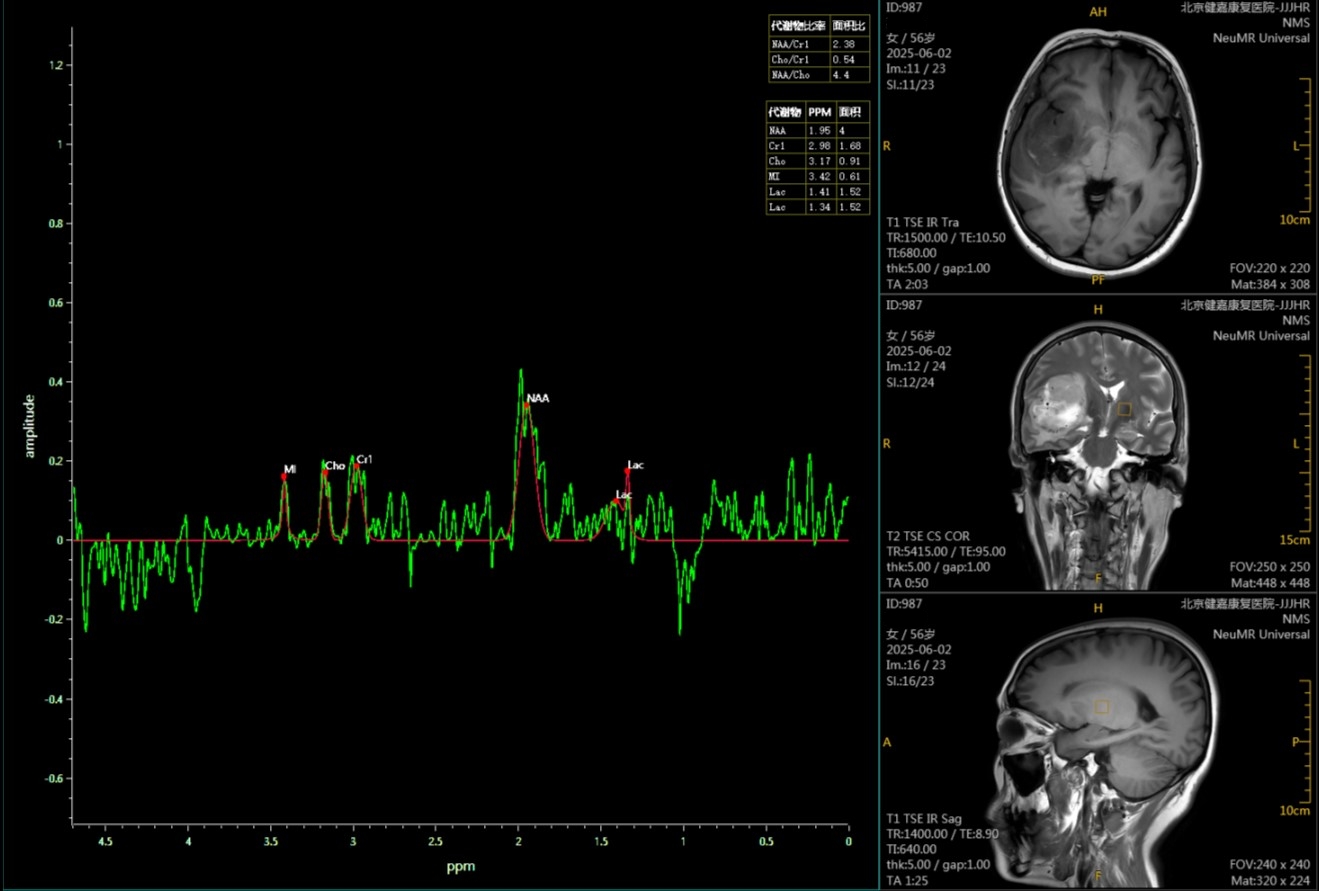

图:右颞叶、岛叶胶质瘤,代谢物NAA下降,Cho略升高,Lac明显升高。

1.N-乙酰天门冬氨酸(NAA):神经元健康指标。它主要存在于健康的神经细胞中。当肿瘤侵袭或破坏神经细胞时,NAA水平会显著降低。

2.胆碱(Cho):细胞增殖指标。胆碱与细胞膜的合成与降解密切相关。肿瘤细胞分裂异常活跃,细胞膜代谢旺盛,因此Cho会急剧升高。Cho的峰越高,通常暗示肿瘤的恶性程度可能越高。

3.肌酸(Cr):细胞能量指标。它参与细胞的能量代谢,在不同组织中都相对稳定。因此,常把它作为内部参考,用其他代谢物(如Cho、NAA)与它的比值来进行分析。

4.乳酸(Lac)和脂质(Lip):无氧代谢与坏死的标志。正常情况下大脑中几乎检测不到它们。它们的出现,意味着肿瘤组织正处于缺氧状态(无氧酵解)或已经发生坏死,这是高度恶性肿瘤的典型特征。